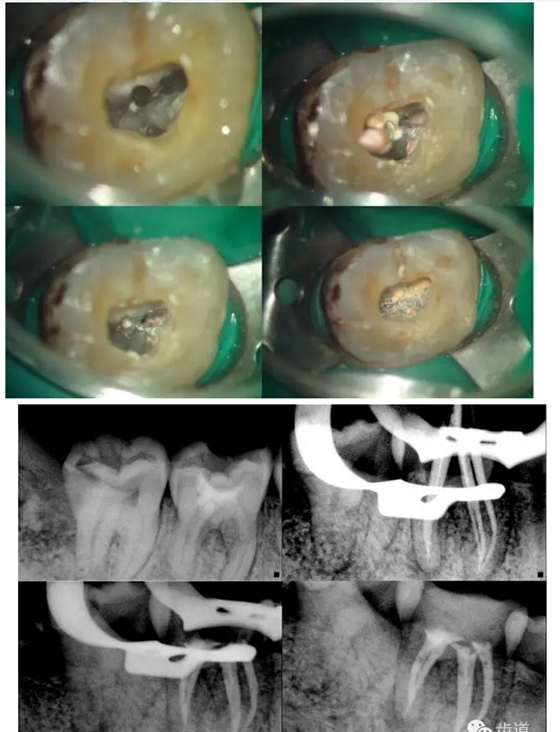

上頜第一磨牙:多為3-4個根管,MB2發(fā)生率約為60%;

下頜第一磨牙:為3-4個根管,遠中雙根管的發(fā)生率為51.4% 左右,側(cè)支根管發(fā)生率為30%左右;

下頜第二磨牙:多為3個根管,C型根管發(fā)生率約為31.5%。